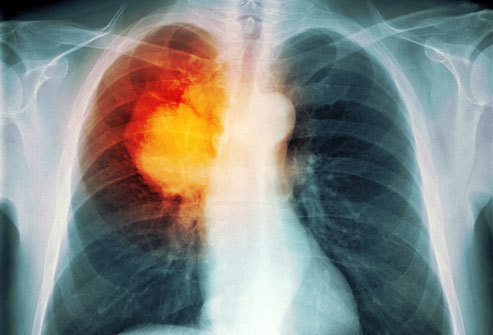

Chẩn đoán ung thư phổi

Trong hầu hết các trường hợp, khi bác sĩ nghi ngờ bệnh nhân mắc ung thư phổi với các triệu chứng điển hình như ho mãn tính hoặc thở khò khè, lúc đó, bác sĩ sẽ cho người bệnh đi chụp X-quang hoặc các xét nghiệm hình ảnh khác. Bệnh nhân cũng có thể được yêu cầu xét nghiệm đờm. Nếu một trong các xét nghiệm cho thấy xuất hiện dấu hiệu của ung thư, bước tiếp theo bác sĩ sẽ tiến hành sinh thiết phổi.